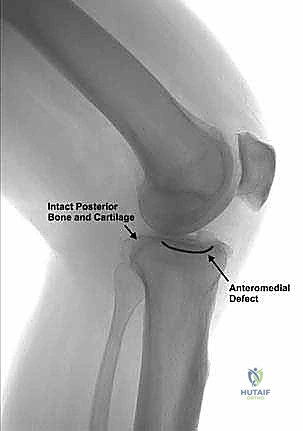

3. الأشعة السينية (X-rays) بوضع الوقوف: وهي الأداة التشخيصية الأهم. يتم أخذ صور أشعة والوزن محمل على الساقين لرؤية المسافة الحقيقية بين العظام. في حالة الخشونة المتقدمة، تظهر الأشعة غيابًا تامًا للمسافة المفصلية في الجزء الداخلي (Bone-on-bone).

صورة طبية: استبدال مفصل الركبة الجزئي (UKA): دليل شامل لمرضى خشونة الركبة الداخلية مع الأستاذ الدكتور محمد هطيف